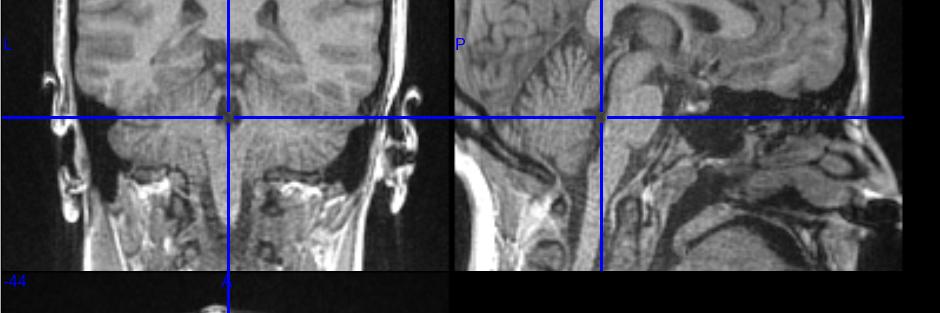

We are proud to announce Benedetta's (🤌) brand new acquisition method: "Hi-Fi fMRI: a novel framework for high temporal resolution Blood Oxygen Level Dependent functional MRI" that she'll present at the poster sessions of OHBM23🧠 check sites.google.com/view/mat-tech-… for the details!